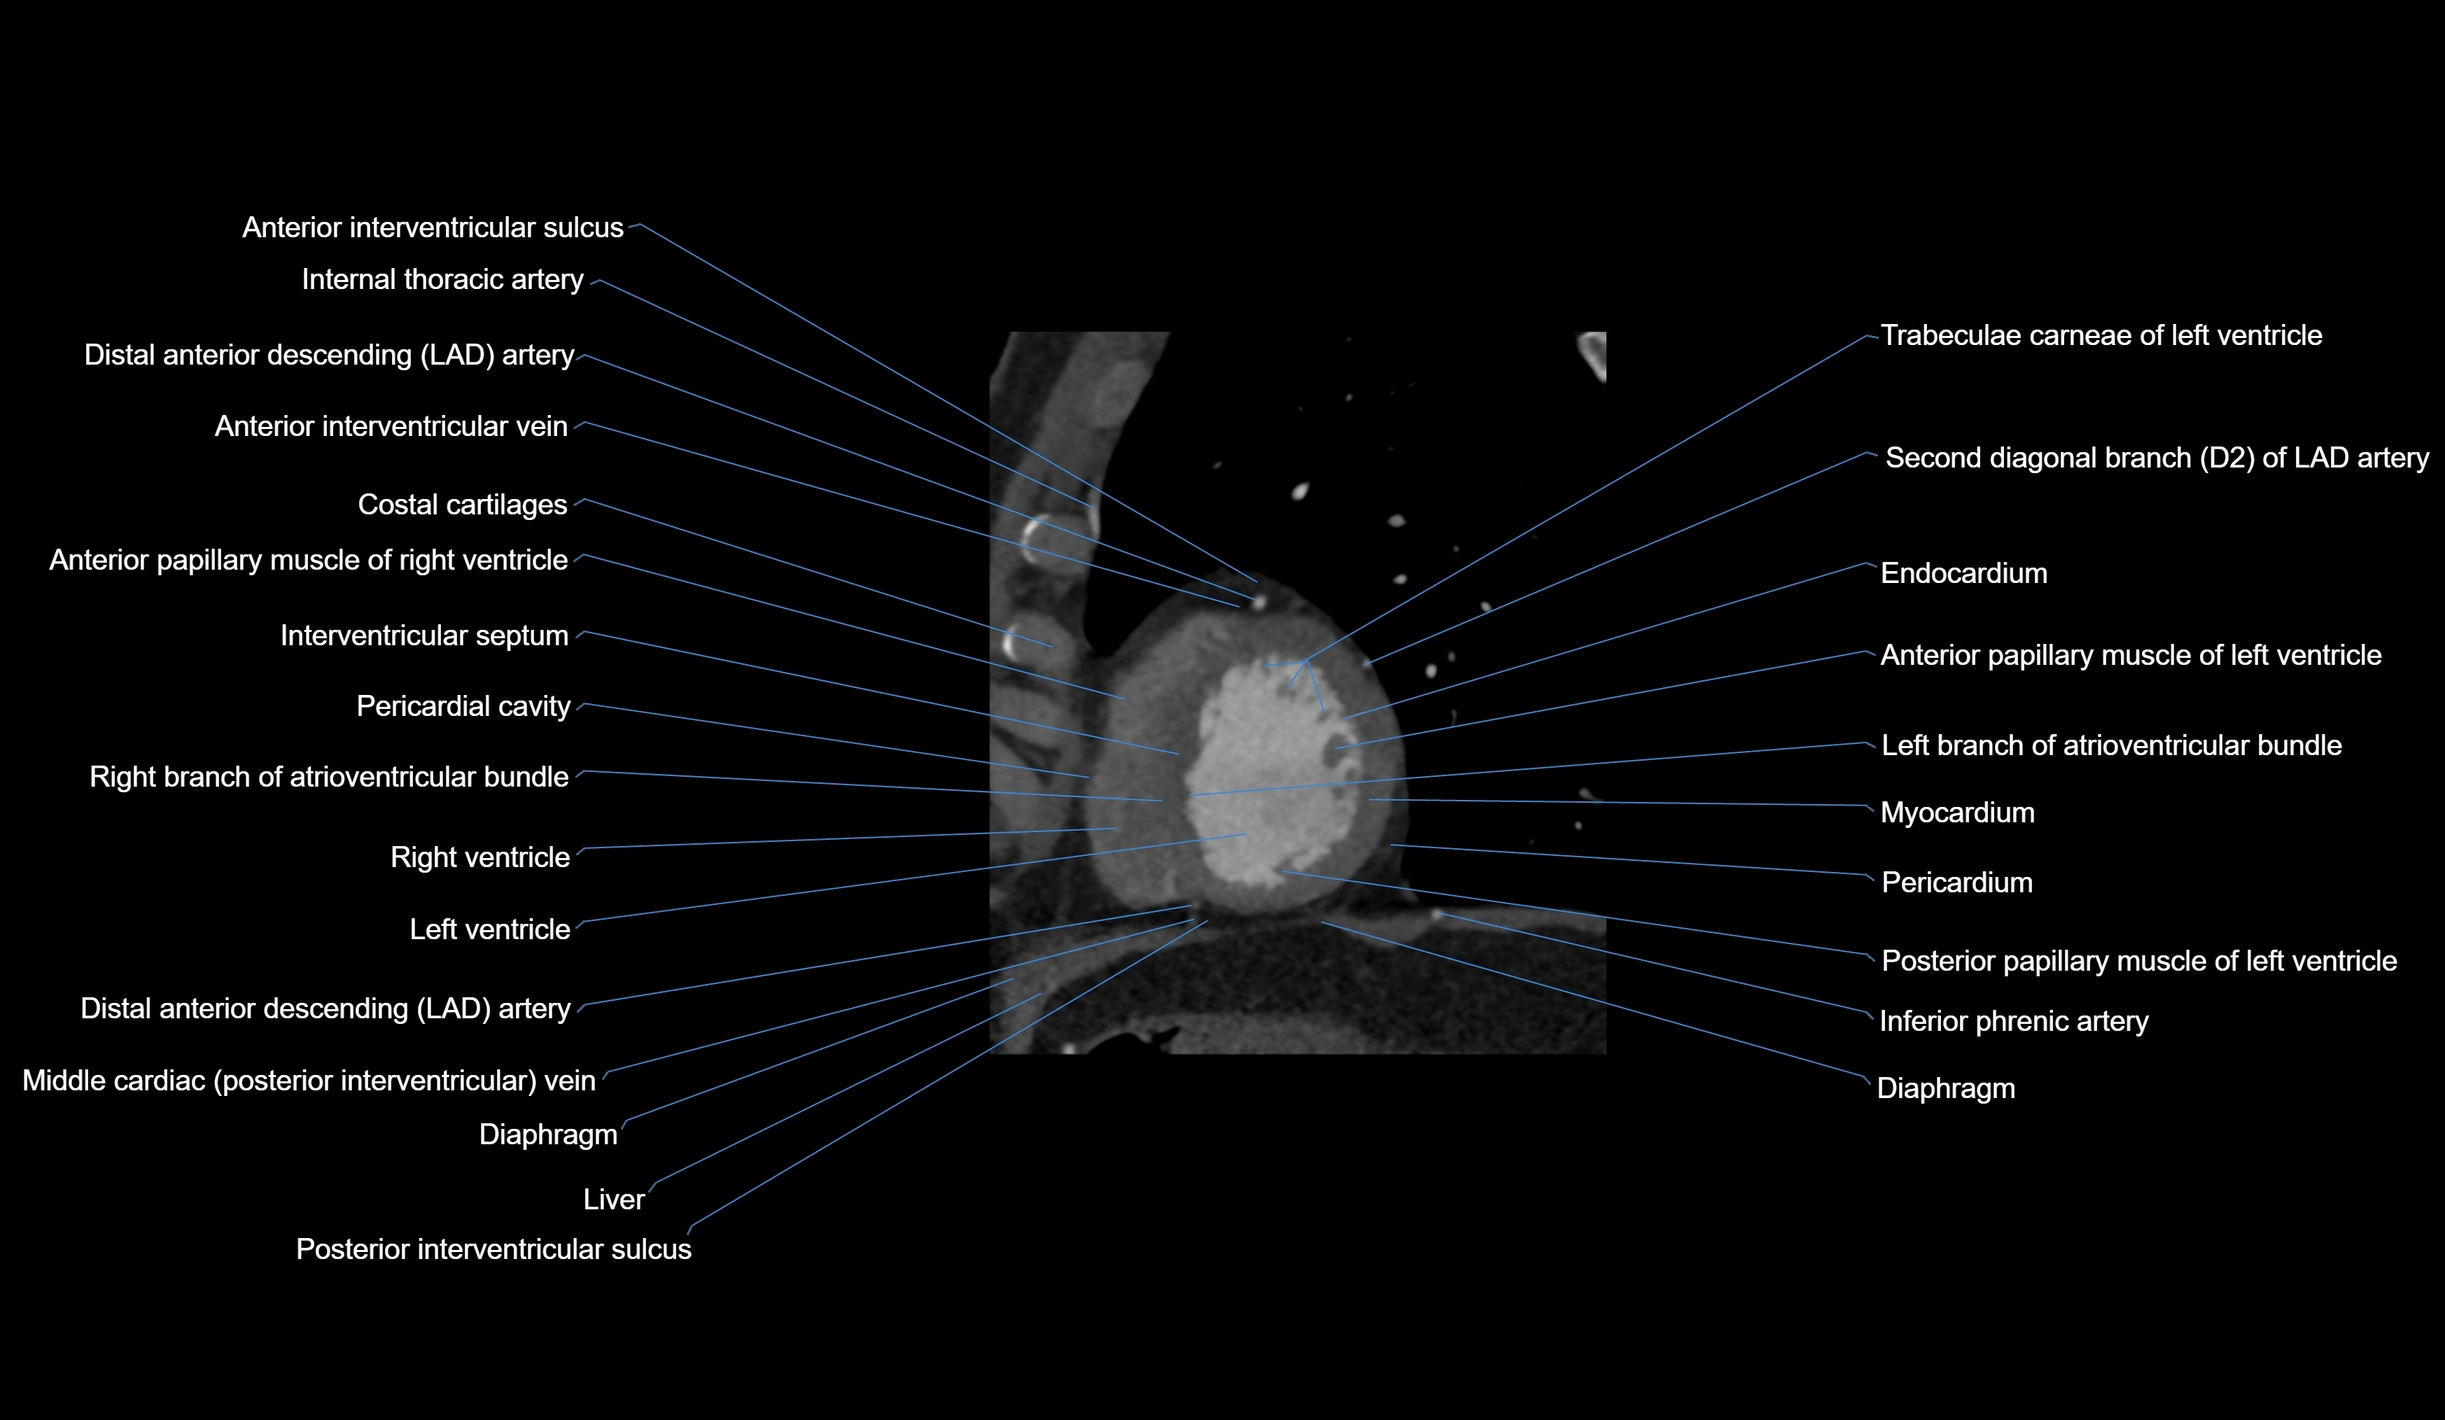

CT Appearance

Non-contrast CT (Calcium Scoring):

-

AM artery visualized for coronary calcium scoring

Calcified plaques appear as hyperdense foci; scored with Agatston method

CT Coronary Angiography (CCTA):

Best non-invasive modality for acute marginal artery visualization

Shows origin, course along the acute margin, and right ventricular branches

Detects stenosis, occlusion, calcified and non-calcified plaques, aneurysm, or anomalous course

Multiplanar reformats and 3D reconstructions help in pre-PCI and surgical planning

Critical for assessing right ventricular infarction risk in RCA disease

MRI image

CT images